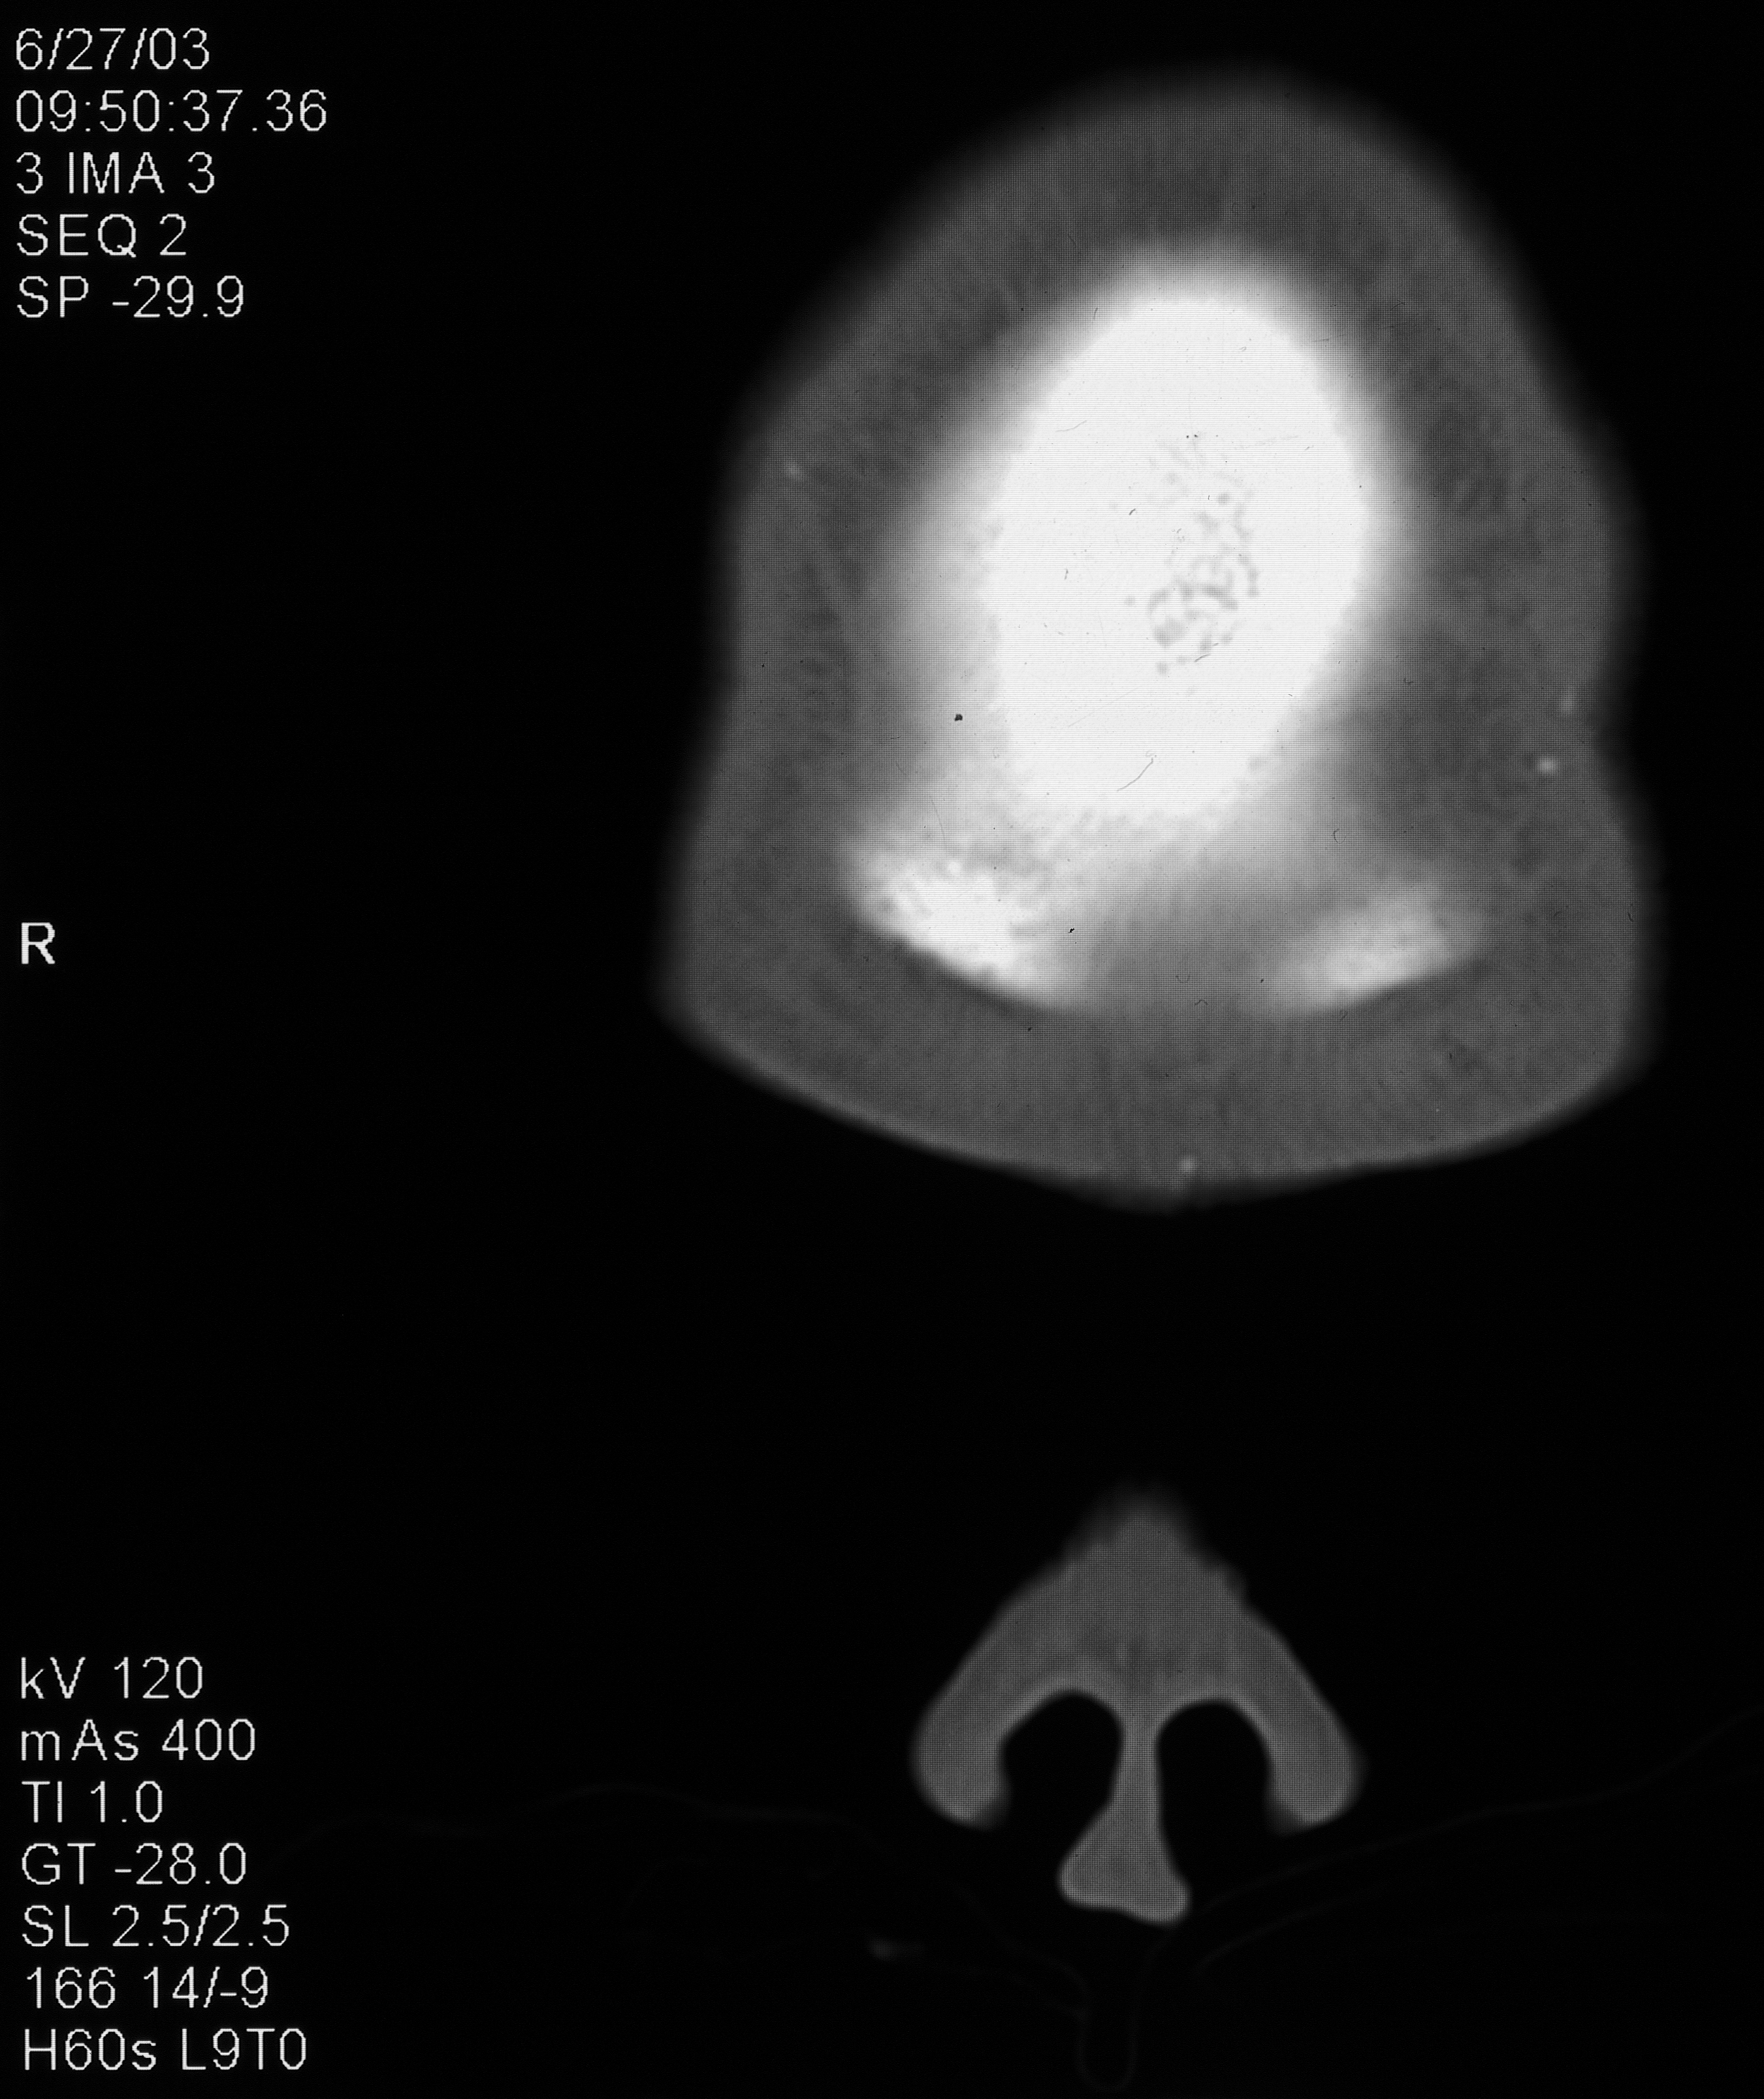

“This is a CT scan of me from June 27, 2003, that shows implanted microchips in my forehead. This is a 1/8″ slice closest to the surface. Notice the circular one on the right side of the scan.”

“This one is from a slice 1/4” deeper, showing the front of my skull. When zoomed in, you can see concentric circles emanating from the circular chip from the transmissions disrupting the CT scan. This chip is transmitting my location and/or my thoughts to the agency monitoring me.